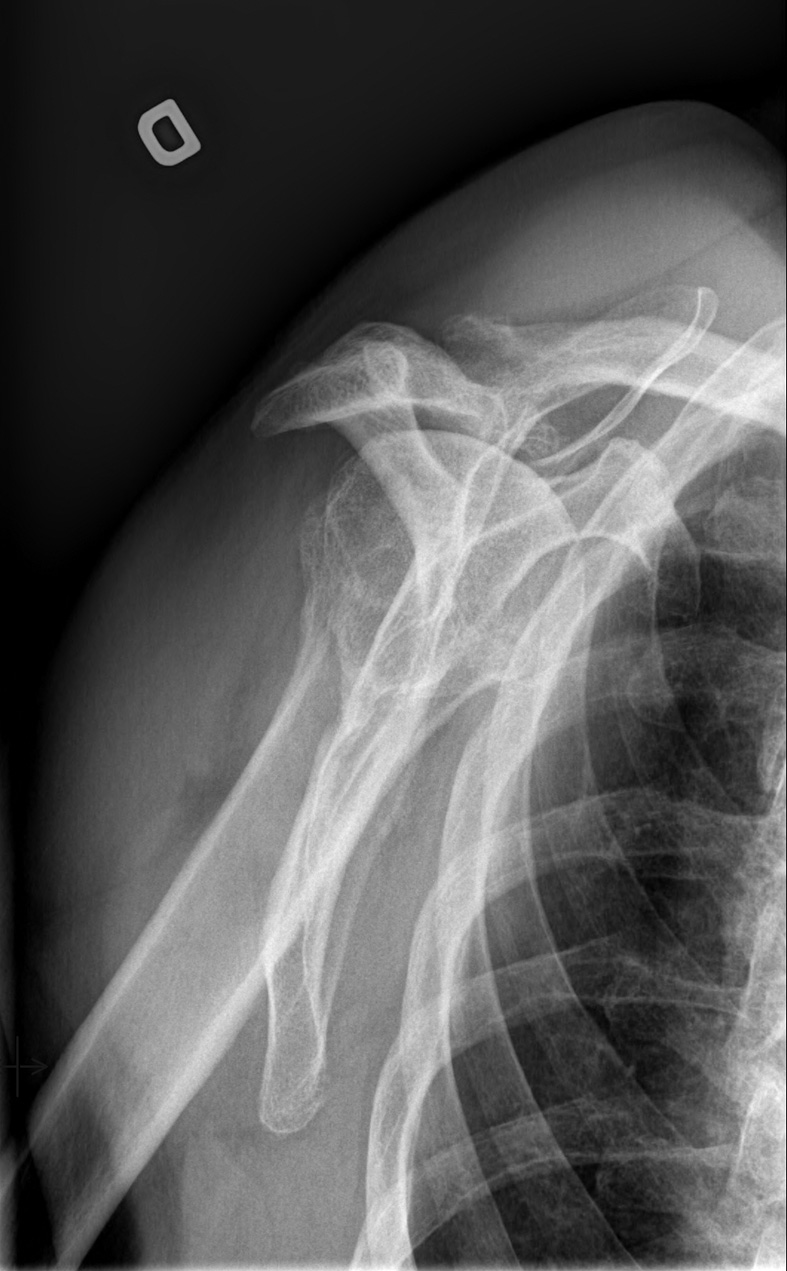

71-year-old male:

Right shoulder pain and stiffness.

Head migration

Rotator cuff tear

Significant humeral head superior displacement, with loss of the acromiohumeral space caracteristic of a massive rotator cuff tear.